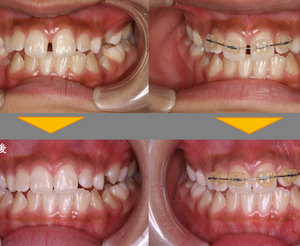

続きを読む小学校6年生の女の子。上の前歯の隙間が気になるので、ここだけを治して欲しいという希望でした。中学校の受験があるので短期間で終わりたいという希望もあり、ブラケットとワイヤーを用いた部分矯正を行いました。 装置は、上の前 ...